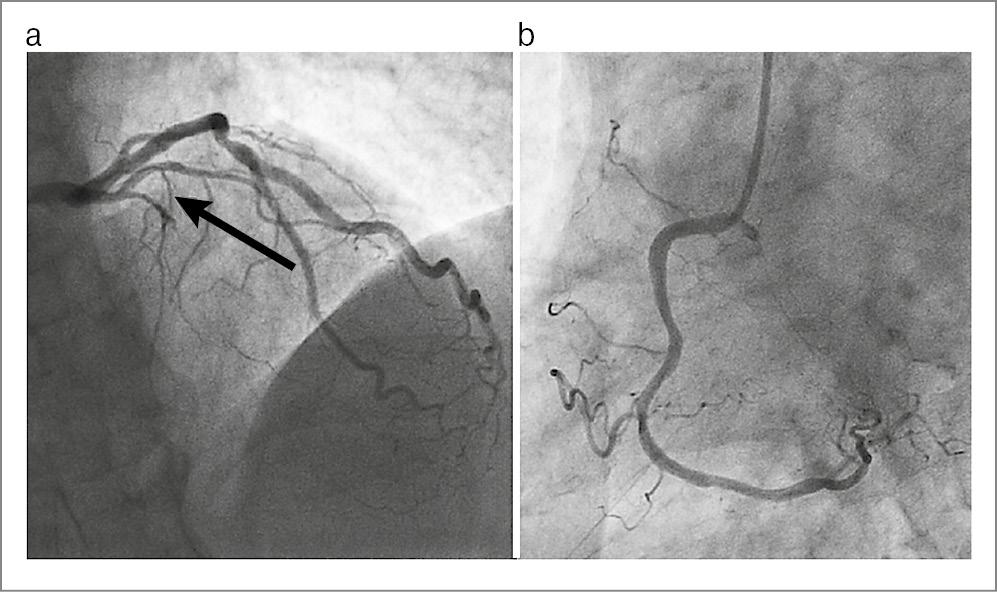

Пациент В., 64 года, обратился за амбулаторной консультацией с жалобами на типичные боли ангинозного характера, возникающие при умеренных физических нагрузках (при ходьбе до 300–400 м, подъеме на 2–3-й этаж) и сопровождающиеся одышкой. Описанные пациентом ангинозные приступы беспокоят его несколько раз в неделю. Купируются самостоятельно или после приема нитроглицерина. В анамнезе у пациента около 10 лет АГ. С его слов, контроль давления он не вел. Полгода назад без предшествующей стенокардии перенес обширный инфаркт миокарда (ИМ) передней локализации. Однако вследствие позднего обращения за медицинской помощью (на 2-е сутки от начала болей) КАГ уже проводили планово. При КАГ выявлена окклюзия передней нисходящей артерии, в остальных магистральных артериях – без значимого стенозирования (рис. 3). Терапия на момент осмотра включала ацетилсалициловую кислоту 100 мг/сут, клопидогрел 75 мг/сут, бисопролол 2,5 мг/сут, спиронолактон 25 мг/сут, сакубитрил/валсартан 50 мг 2 раза в сутки, дапаглифлазин 10 мг/сут, розувастатин 40 мг/сут. При осмотре отсутствовали признаки застойной сердечной недостаточности, обращала на себя внимание выраженная гипотензия (100/70 мм рт. ст.), которая, со слов самого пациента, появилась после перенесенного ИМ и носит постоянный характер.

Рис. 3. Ангиограмма левой коронарной артерии пациента В.: a – левая коронарная артерия, стрелкой помечена окклюзия передней нисходящей артерии; b – правая коронарная артерия без значимых стенозов.